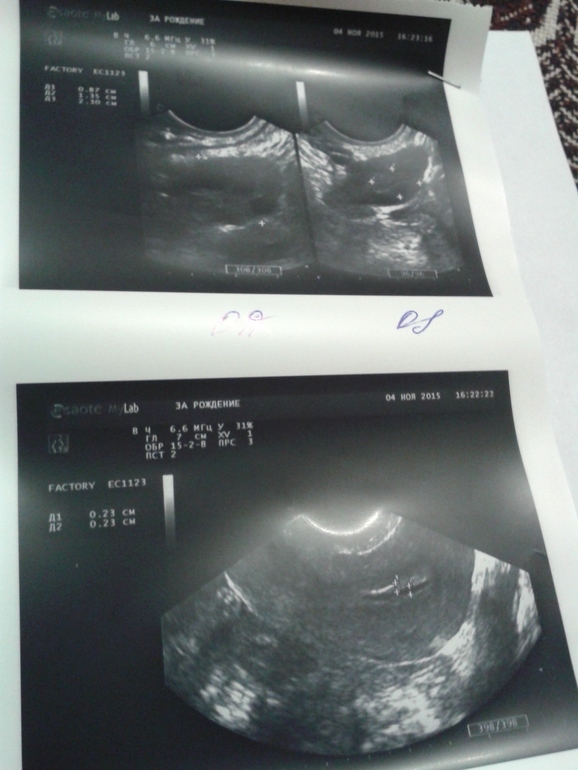

ФолликулометрияДевочки, привет. Сегодня ездила на узи на 5 день цикла. Посмотрите пожалуйста все ли в порядке.я не понимаю, а врач ничего не сказала

эндик очень тонкий для 5 дц, обычно он уже 4-6 мм, а у вас как будто 2 дц

в матке еще кровь - монстры у вас еще идут

с прошлого цикла остался жт, не рассосался - бывает, не работает он

есть фолликул в ля 8 мм самый большой

Вот и я подумала что маленький. Сравнивала с июньским узи. Там был 8 эндометрий. С июня пью дюфастон. А как нарастить хоть немного?

у вас осталось желтое тело...по идее оно должно было исчезнуть после М..это у рача лучше уточнить...

но по УЗи она мне сказала что все хорошо. Про эндометрий мне ничего не сказала, а мне кажется что он маленький.